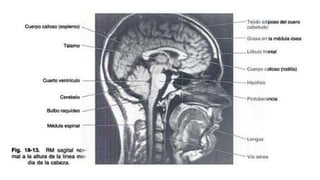

Resonancia Magnética

Ofrece una diferenciación entre la sustancia gris y la sustancia blanca

todavía mayor que la TC. Permite la obtención de imágenes directas en

los planos coronal y sagital. LCR aparece negro, aunque el hueso cortical

se muestra negro, la grasa y cuero cabelludo son muy blancas